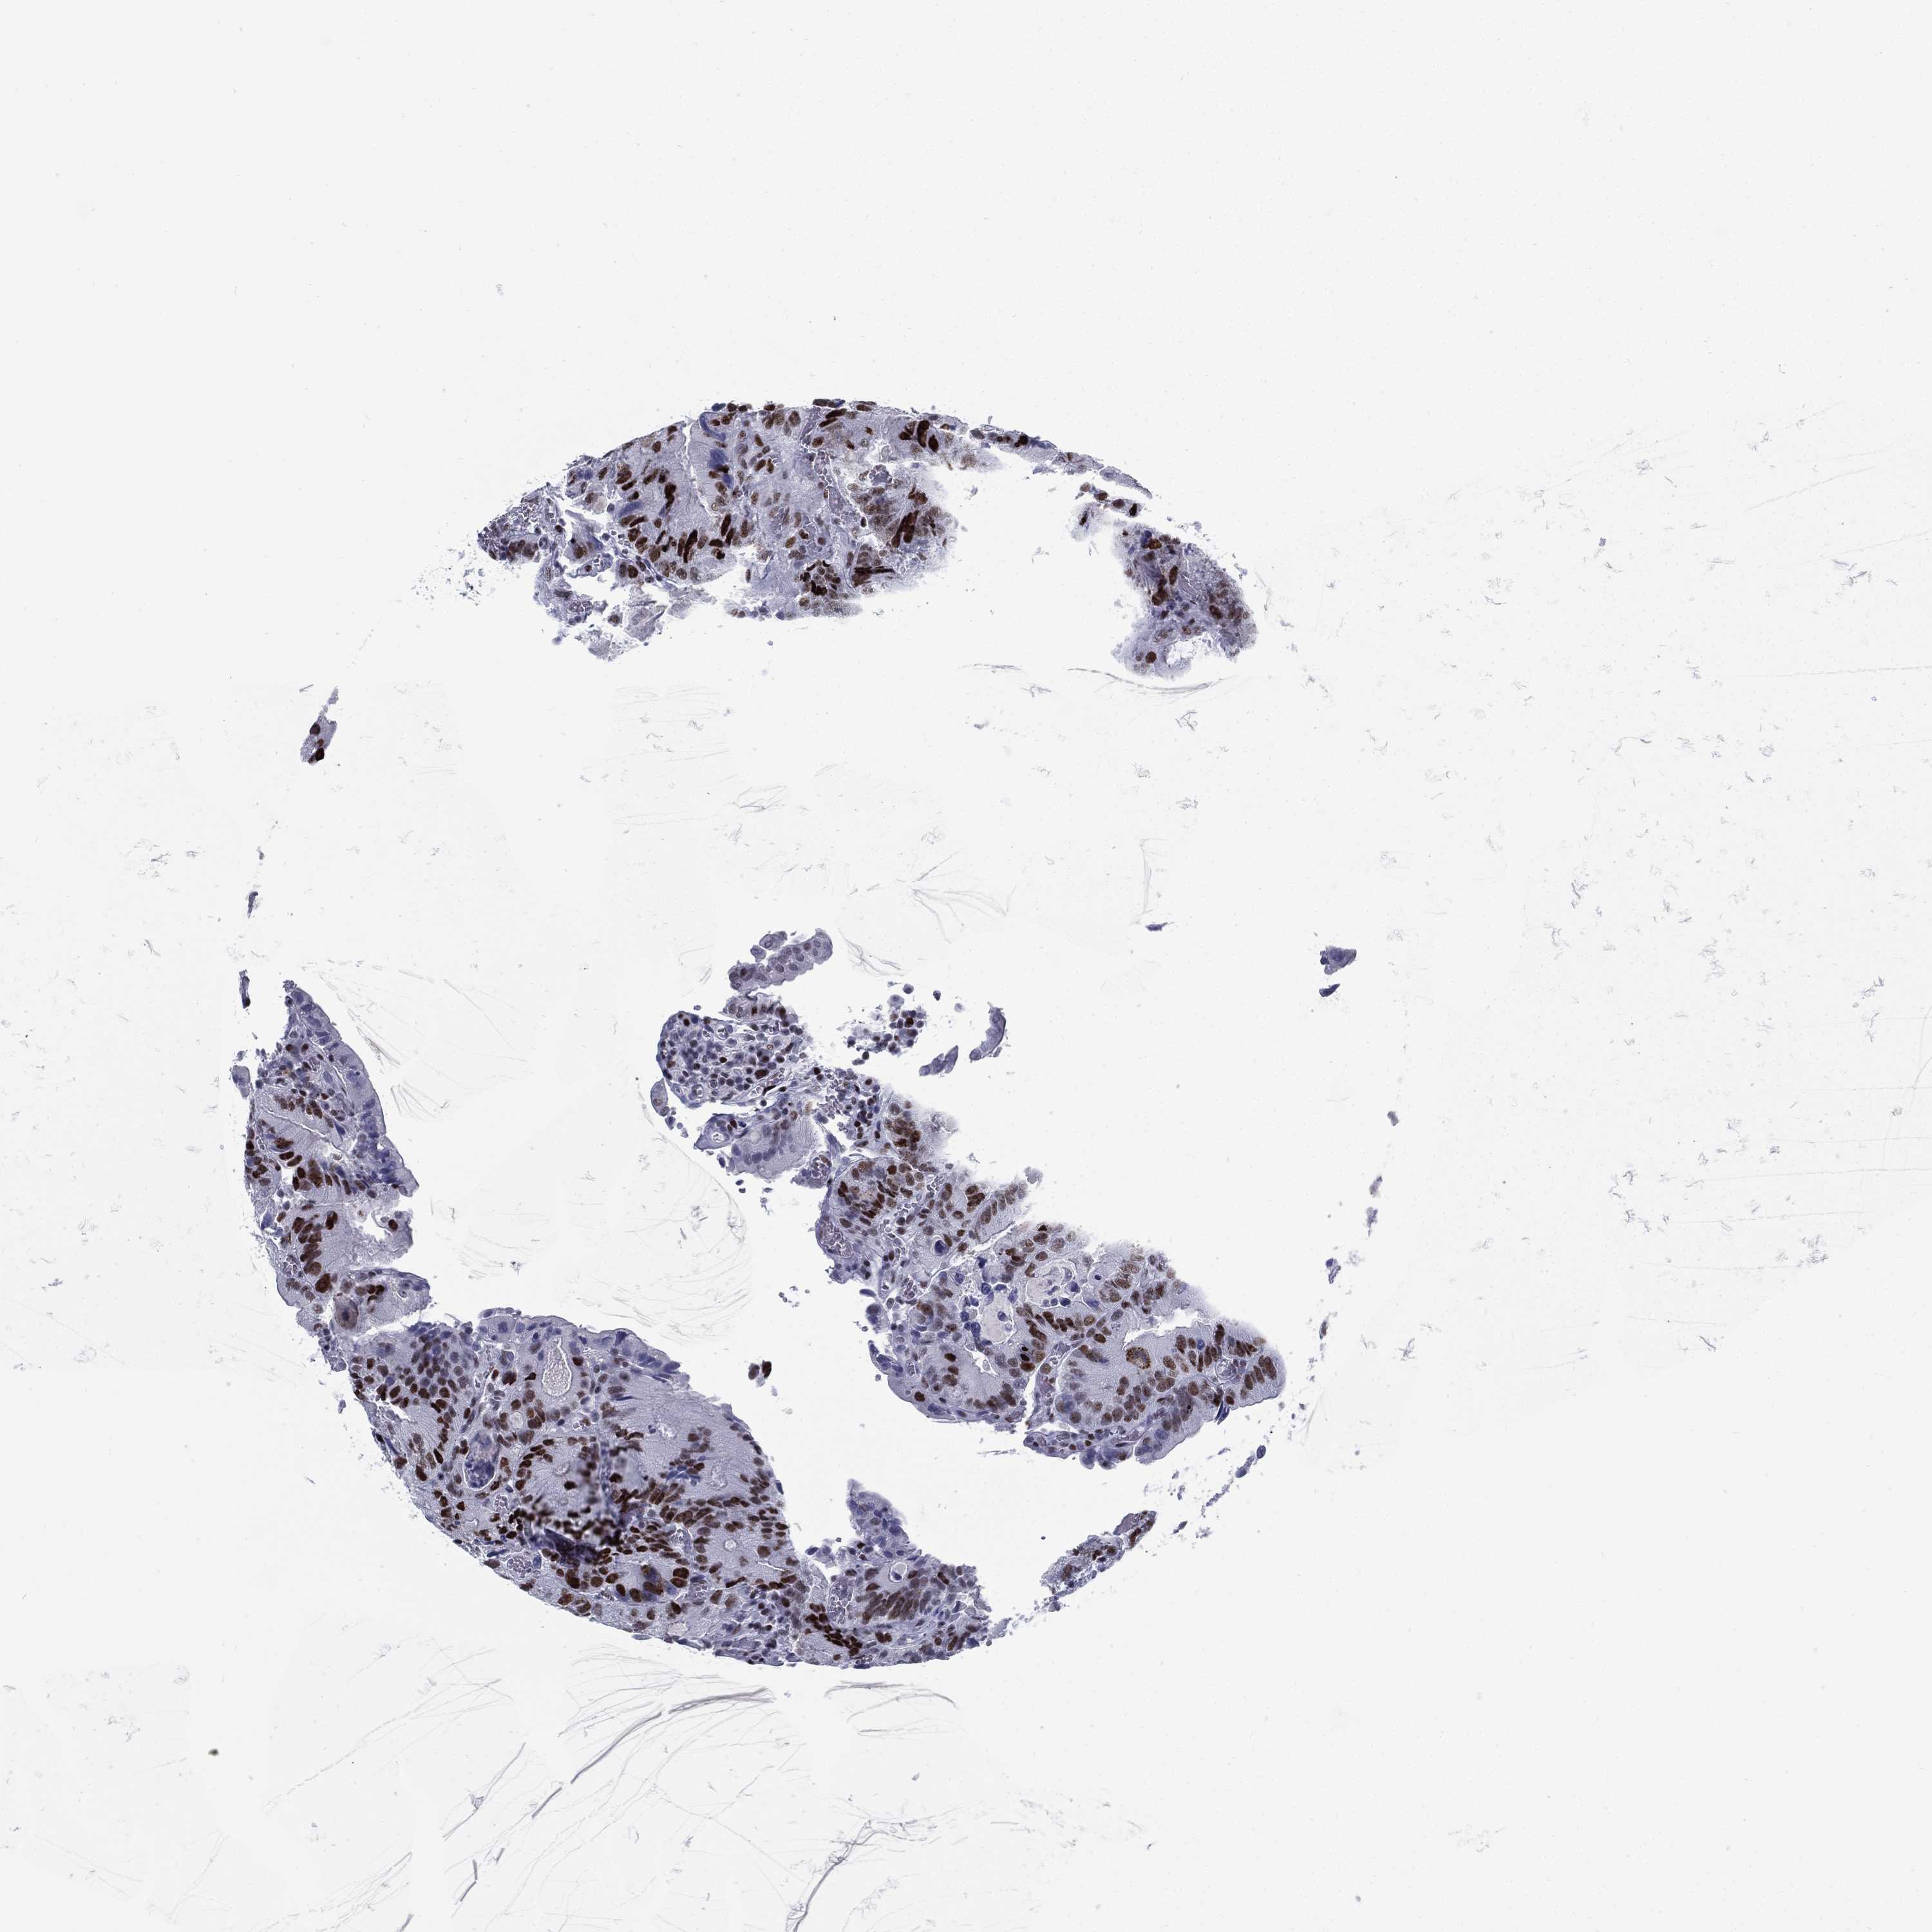

CANCER COLORECTAL CANCER Show tissue menu

Colorectal cancer

Colon adenocarcinoma